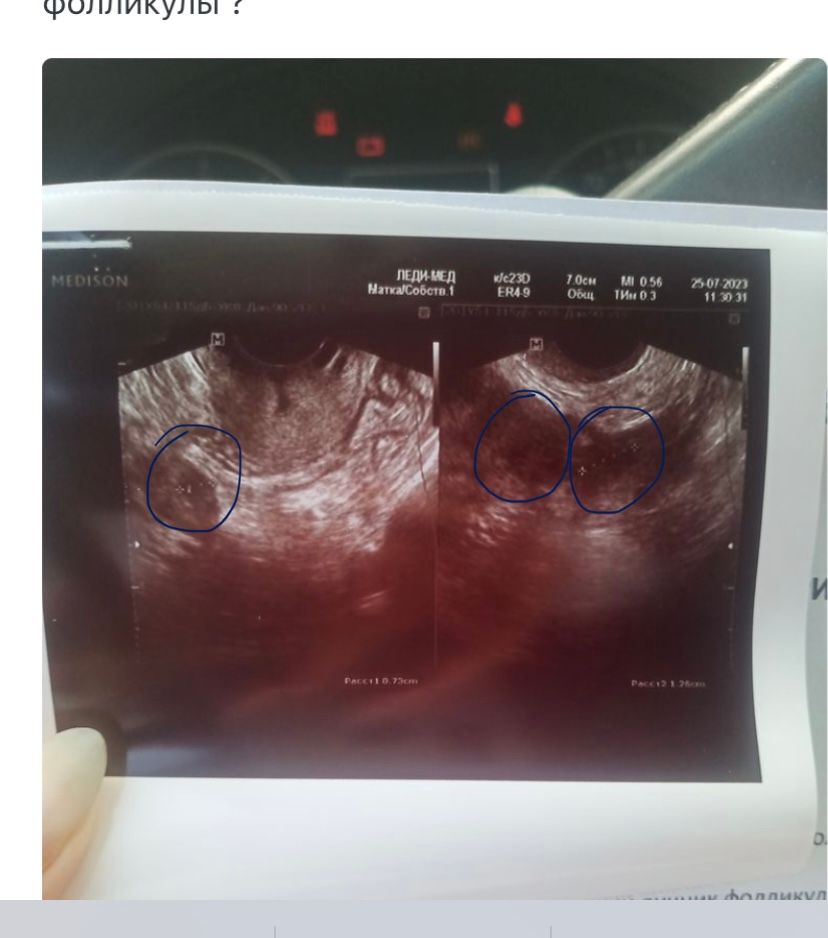

Где на фото узи фолликулы ?

Темные пятна округлой формы с визуально улавливаемыми границами. Они у вас замерены - границы обозначены крестиками, пунктир между ними - диаметр, в правом нижнем углу размер обозначен. Но снимки не очень, плохо видно. Изображение

А внизу под каждым фото размер их написан

Они у вас там стрелочками выделены даже